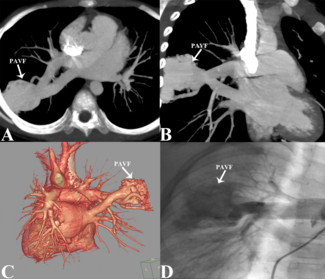

Leizhi Ku, MD; Mei Wu, MD; Juan Xia, MD; Yafeng He, MD

A 39-year-old woman presented with a recurrent headache and dizziness for 6 months. Physical examination and laboratory tests were unremarkable, and the electrocardiogram indicated sinus rhythm.

11/27/2024

Journal of Invasive Cardiology